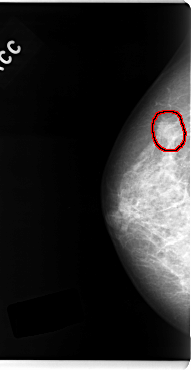

C_0127_1.RIGHT_CC

RIGHT_CC LINES 4808 PIXELS_PER_LINE 2480 BITS_PER_PIXEL 12 RESOLUTION 50 OVERLAY

FILE: C_0127_1.RIGHT_CC.OVERLAY

TOTAL_ABNORMALITIES 1

ABNORMALITY 1

LESION_TYPE MASS SHAPE IRREGULAR MARGINS ILL_DEFINED

ASSESSMENT 4

SUBTLETY 4

PATHOLOGY MALIGNANT

TOTAL_OUTLINES 1

BOUNDARY